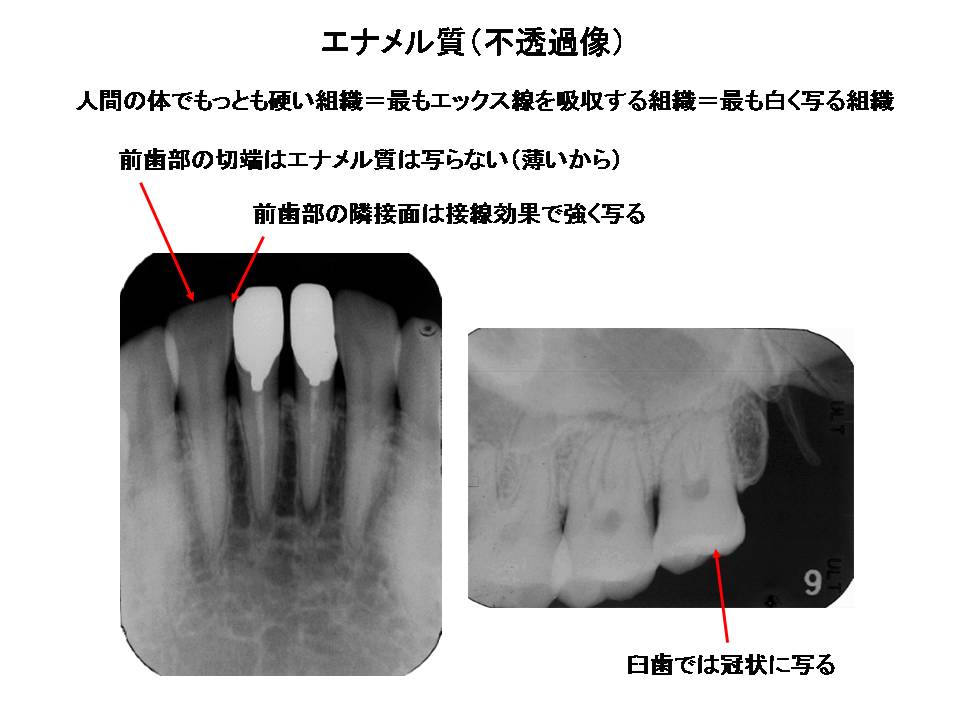

HOT ! デンタルエックス線写真 口内法(二等分法・咬合法)撮影の解剖

デンタルエックス線写真 口内法(二等分法・咬合法)撮影の解剖の詳細情報

口内法(二等分法・咬合法)撮影の解剖。zu31.jpg。究極の先に見えたもの ~Veraview X800~ | コミュニケーターだより。デンタルエックス線写真斉田 寛之クインテッセンス出版書き込み等もなく比較的綺麗な方かと思います。治療の道しるべ、X線写真について | サン・スマイル歯科。

• 口内法(二等分法・咬合法)撮影の解剖

• zu31.jpg